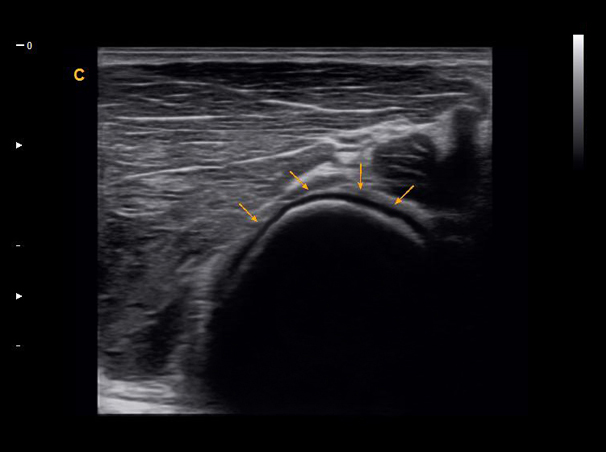

Subscapularis Tendon, B Mode